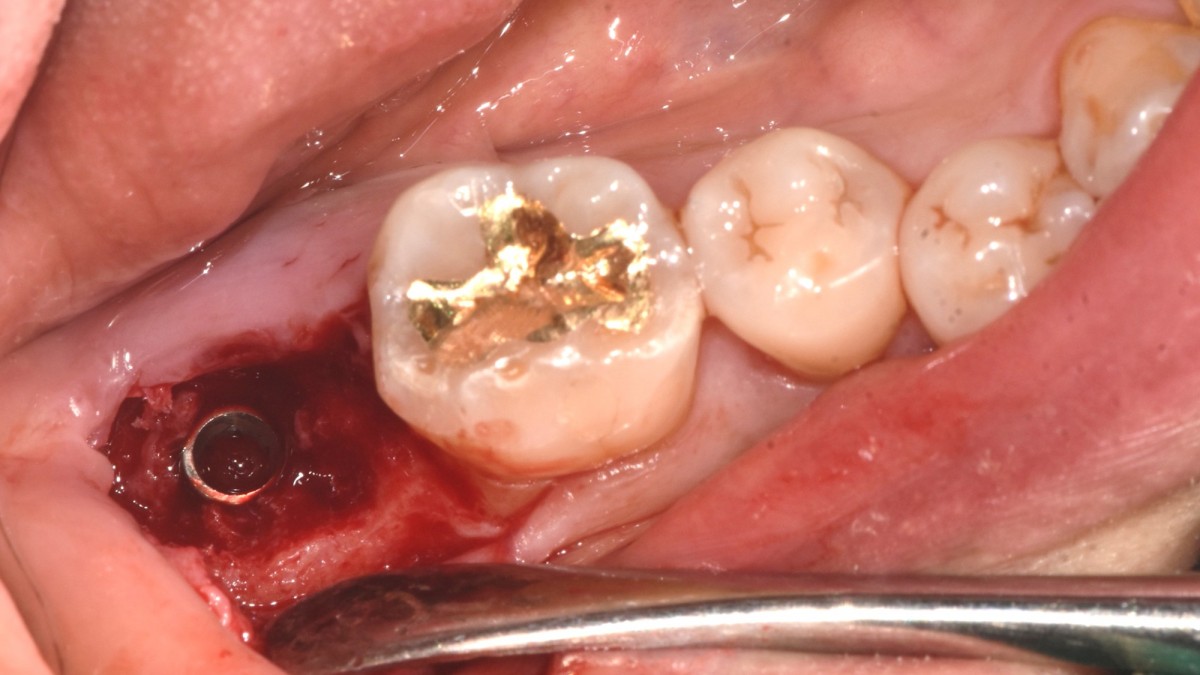

Single implant (staged) Arum NB1, f/u

A 47-year-old male patient had a crown with an ill-fitting margin and crack-tooth syndrome in the lower 2nd molar. No systemic issue.